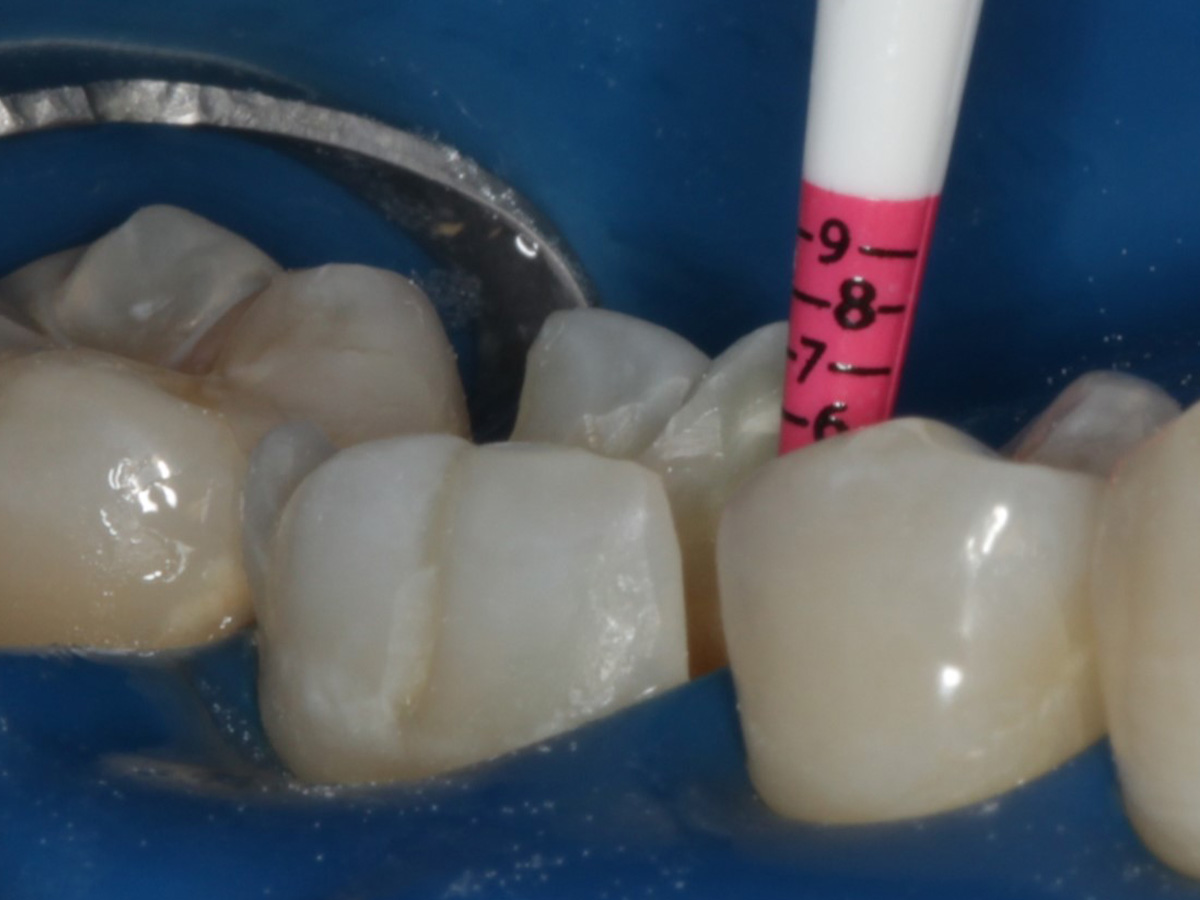

Abbildung 10

Height Indicator vor Auswahl der passenden Evolve Matrize distal

Abbildung 11

Height Indicator vor Auswahl der passenden Evolve Matrize mesial